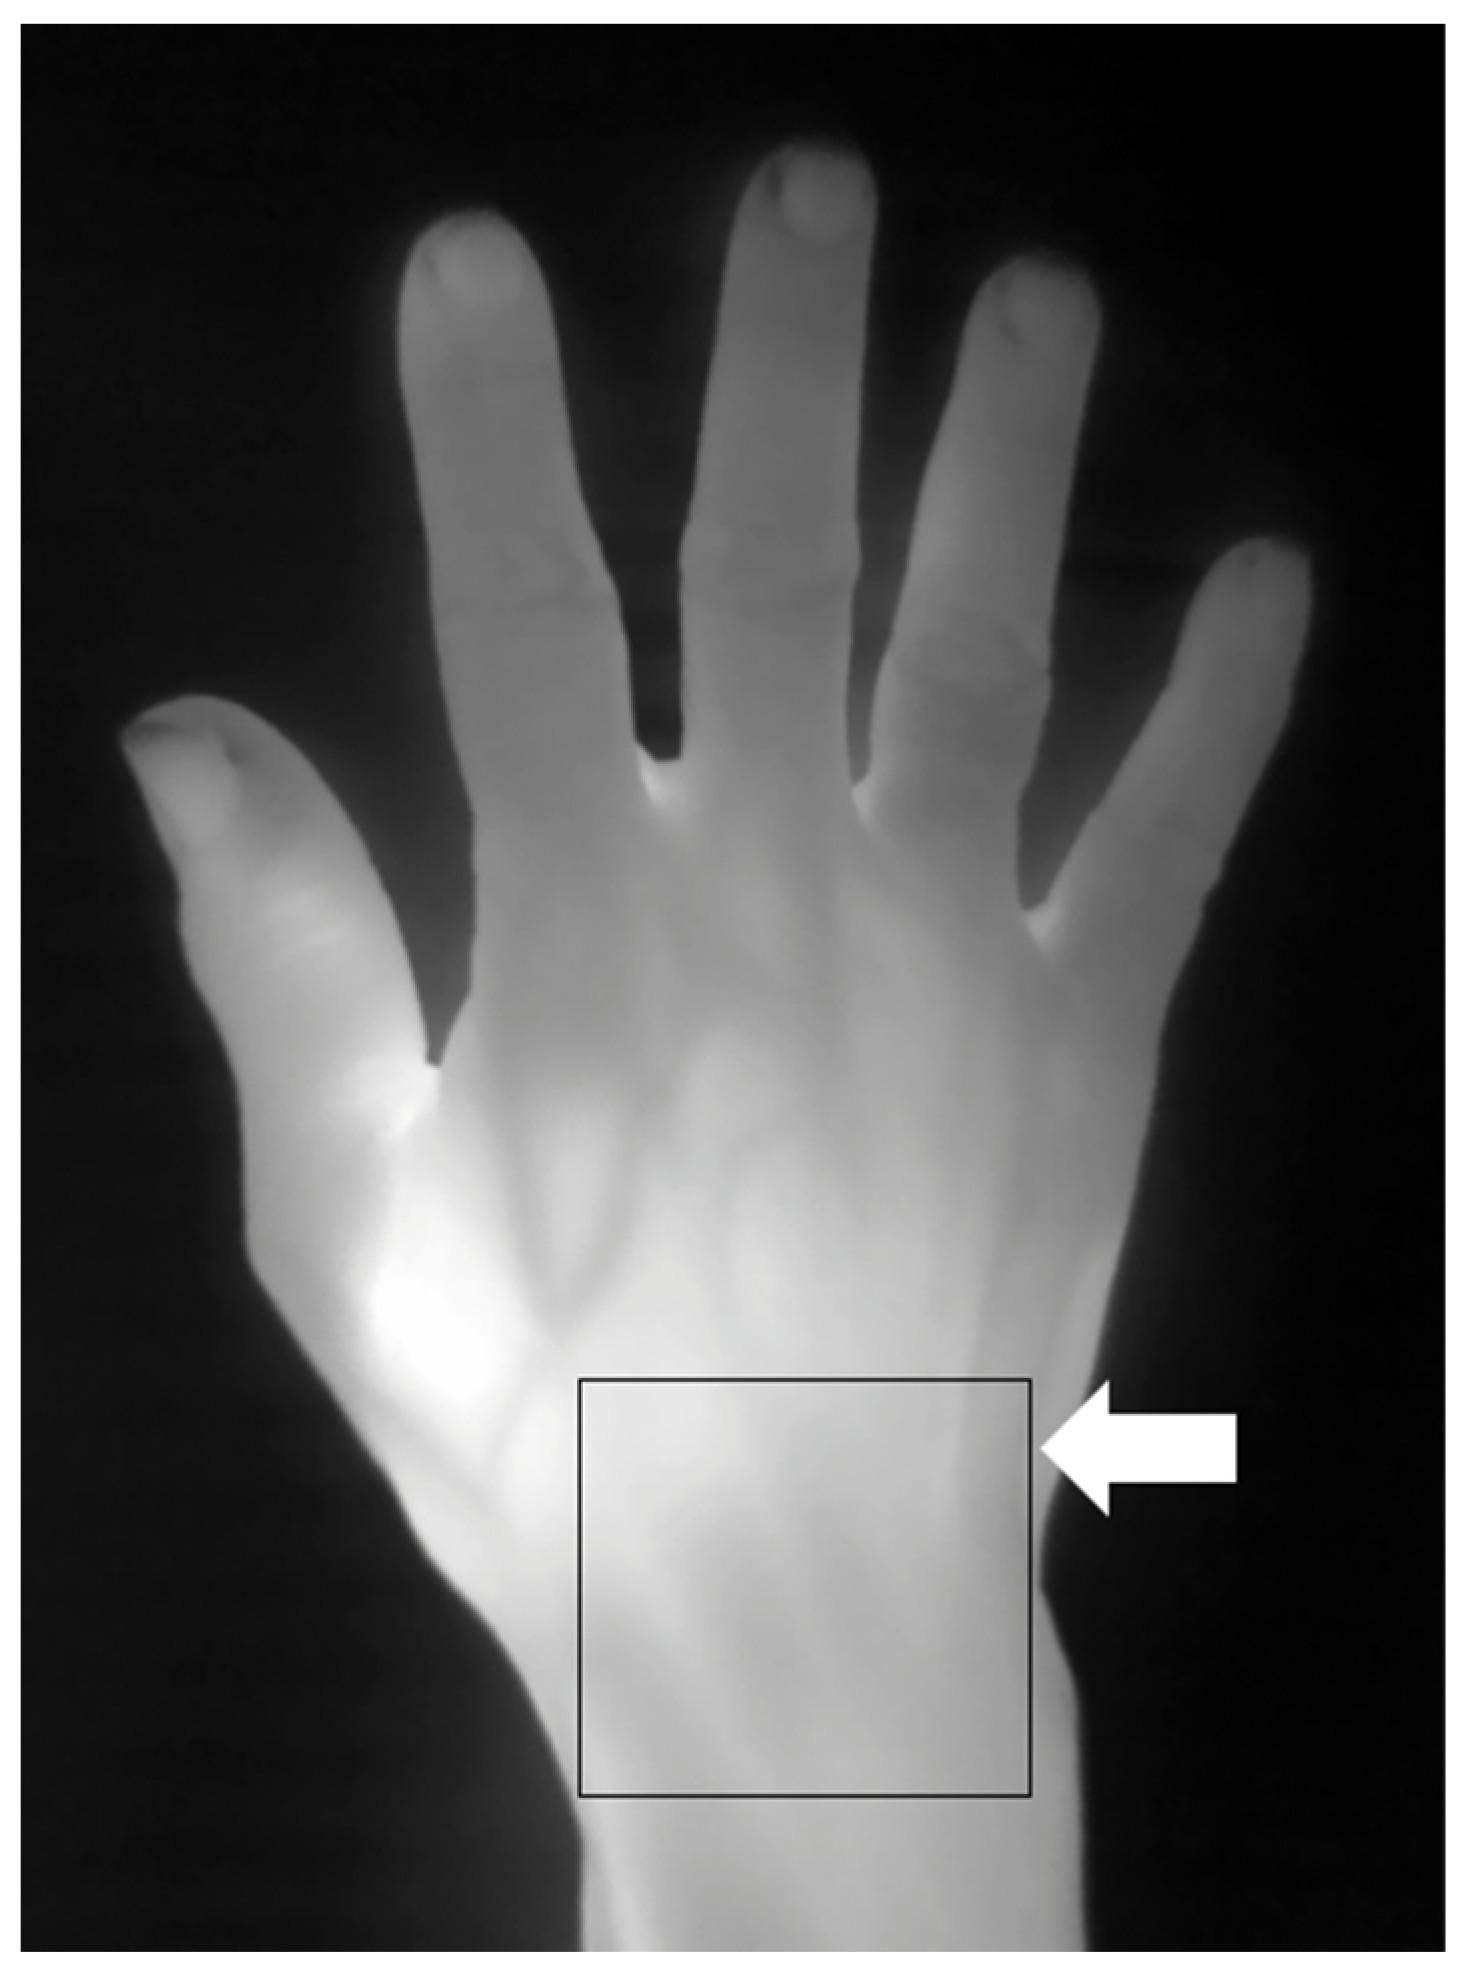

Thermography followed established imaging methods previously described in the literature [19,26,27]. Standardized thermal imaging was conducted in a draft-free room (without windows) with an ambient temperature of around 23 °C [26]. A high-performance portable thermal camera FLIR T640 (FLIR Systems AB, Sweden) was utilized for thermal imaging with the following thermal camera settings: predefined emissivity value of 0.98 for skin [19]; thermal sensitivity of <30 milli-Kelvin (mK) at 30 °C; pixel resolution 640 × 480). As per usual practice, before thermal imaging was carried out, patients were rested for 15 min to allow for acclimatization [26]. Physical objects (such as jewelry and watches) obscuring the view of the thermal camera were removed. The patient’s hands (neutral position) were placed on a flat tabletop. The dorsal view of the hand was imaged with the thermal camera placed 50 cm above the hand. Using a region of interest (ROI) [19,27,28] manual segmentation approach (see Figure 2 for an example of ROI manual segmentation for thermography), rectangular boxes representing the ROIs were placed over the target joint sites (e.g., the wrist, MCPJ, etc.) and the corresponding thermographic temperatures (maximum (Tmax), average (Tavg), minimum (Tmin) temperatures) at the ROIs recorded for further analysis.

Figure 2.

Thermography showing a right-hand thermogram. Example of thermal imaging assessment (arrow showing region of interest (ROI) manual segmentation) at the dorsal aspect of the wrist.